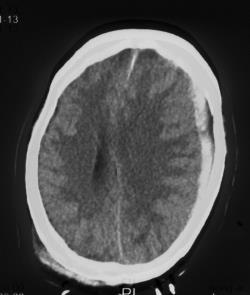

复阅2018年5月9日CT片:右枕顶部软组织肿胀、密度增高,右枕骨见线状骨质断裂、骨折线累及斜坡,右枕部颅板下见梭形致密阴影,大脑镰旁见线状致密阴影,左额颞部颅板下见弧形致密阴影,右额叶及左额颞叶均见斑片状高低混杂密度影,尤以左额叶明显,右侧小脑见斑片状高低混杂密度影。提示右枕顶部头皮血肿,右枕骨骨折,右枕部硬膜外血肿,蛛网膜下腔出血,右颞部硬膜下血肿,右额叶及左侧额颞叶脑挫裂伤,右侧小脑挫裂伤。

图1-5,2018年5月9日 CT片,右枕顶部头皮血肿,右枕骨骨折,右枕部硬膜外血肿,蛛网膜下腔出血,右颞部硬膜下血肿,右额叶及左侧额颞叶脑挫裂伤,右侧小脑挫裂伤